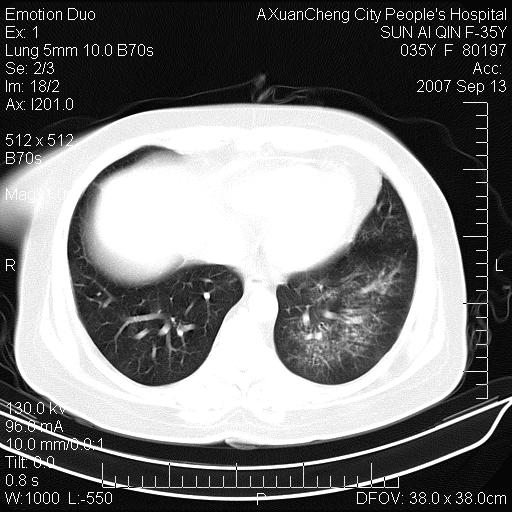

以下是引用天南地北在2007-9-13 13:43:00的发言:[br]考虑双肺、肺门侵润

以下是引用ydx_74在2007-9-13 15:42:00的发言:[br]仅看片,考虑右上肺癌并双肺转移,结合病史,考虑肺门、肺内淋巴侵润

以下是引用同在2007-9-13 15:08:00的发言:[br]支持肺门及双肺侵润.